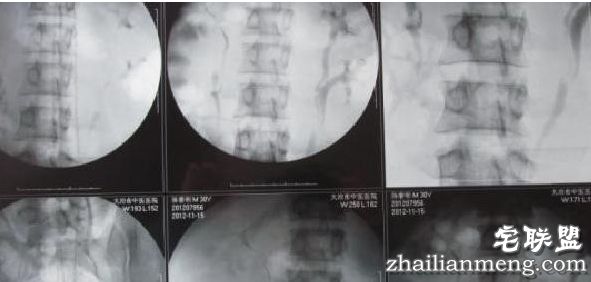

进一步检查后发现,陈先生左、右两个肾脏上部,各多长了一个“肾”。该医院徐医生表示,其身上的“重复肾”,其实是肾、输尿管的先天畸形,检查得知,其多出来的“两颗肾”内均清晰可见流动的血液和尿液。经过治疗,目前位于陈先生右输尿管上段的一颗4×10mm的结石已部分击碎,有待复检和进一步观察。

有资料显示,重复肾的发病率约为1500:1,而这其中,类似陈先生这种双侧畸形的发病率仅为单侧畸形的六分之一。

对此,陈先生非常惊讶:“我活了30年,直到这时,才知道自己长了四个肾。”陈先生长了四个肾,是先天性生理现象。从目前的检查情况看,这四个肾的总体功能,与正常人的两个肾没有多大区别。医护人员正在积极治疗他的病。